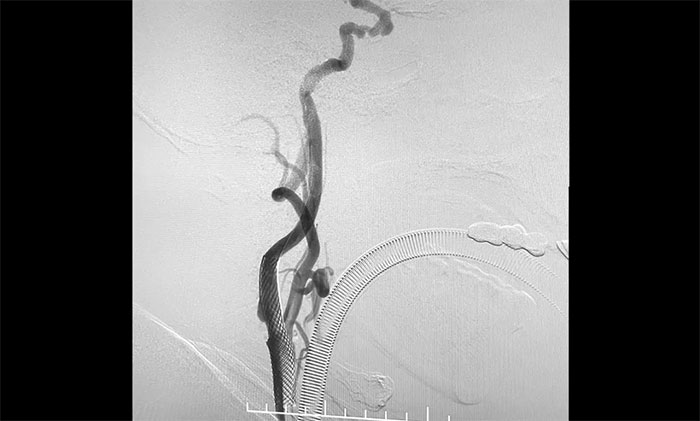

术中,席刚明教授、王贵平博士先对左颈内动脉起始段重度狭窄处进行开通治疗,在保护伞下经过多次球囊扩张后,顺利释放支架于左颈内动脉起始段至左颈总动脉末段,造影见狭窄明显改善,顺利开通血管。

▲ 颈动脉重度狭窄解除,打通大脑生命线